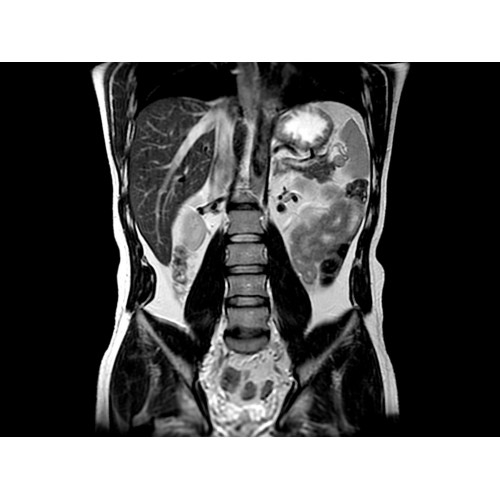

• Комплексная оценка печени — первая в отрасли ИП MR-Touch открывает новые возможности диагностики благодаря способности определять различия в жесткости тканей.

Пациентам с такими хроническими заболеваниями печени, как фиброз и цирроз, часто требуется регулярное наблюдение гастроэнтеролога. Это может потребовать проведения инвазивных процедур, которые не всегда позволяют получить полную информацию о состоянии печени.

Новая ИП MR-Touch, разработанная компанией GE совместно с клиникой Майо, основана на исследовании печени с помощью акустических волн, в ходе которого выявляются различия в жесткости тканей. Результатом исследования является эластограмма, полное изображение печени. По таким эластограммам радиологи и гастроэнтерологи могут периодически контролировать состояние пациента и принимать информированные решения о терапии. Более того, данная методика открывает новые возможности и позволяет оказывать инновационные услуги имеющимся пациентам и привлекать новых клиентов.